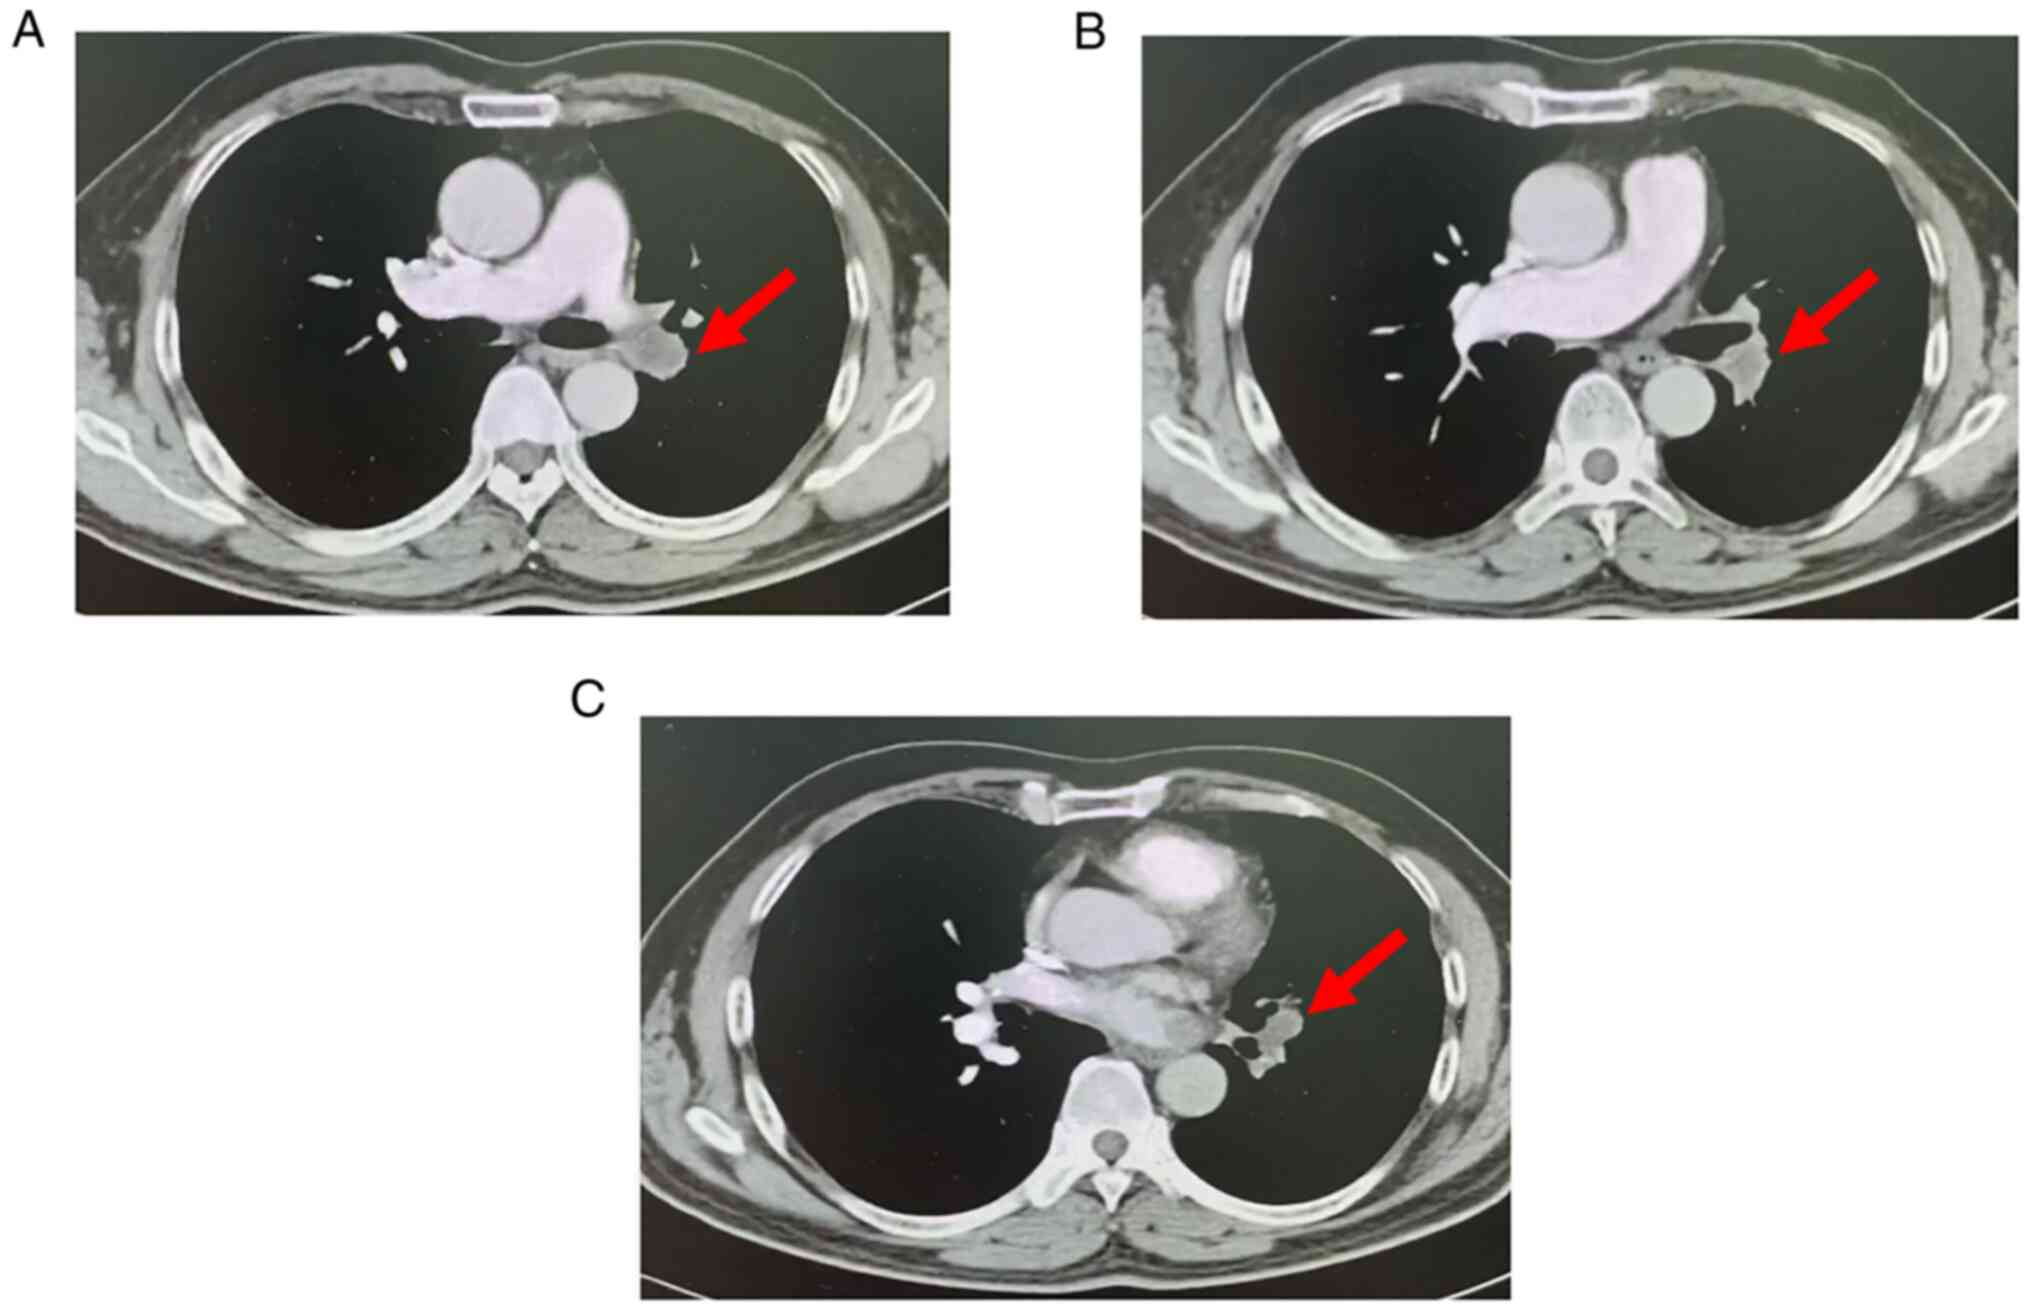

During the hospitalization period, right heart catheterization, which is a possibly helpful test for cases with similar presentation, e.g. to rule out the possibility of chronic thromboembolic pulmonary hypertension, was planned. However, the patient did not consent to undergo this examination. Re-examination of the pulmonary artery CTA (Fig. 3) revealed that the left pulmonary artery was completely embolized, whereas the right main and middle pulmonary arteries were partially embolized. Lung perfusion imaging (Fig. 4) indicated that blood perfusion was reduced in the majority of the left lung and in the anterior segment of the right upper lobe, which was consistent with pulmonary embolism. The patient underwent CT-guided percutaneous puncture biopsy and positron emission tomography (PET)/CT (Fig. 5), which revealed the following: Soft tissue mass in the area of the left pulmonary artery and slightly increased metabolism; space-occupying upper lobe of the left lung, slightly increased metabolism; nodules in both lungs; left hilum lymph nodes, increased metabolism; thickened left pleura with a small amount of effusion in the left pleural cavity.

Figure 3.

Pulmonary artery CTA examination following 6 months of anticoagulation treatment. Small nodular filling defects were observed in (A) the right main pulmonary artery (red arrow) and (B) right middle pulmonary artery (red arrow). (C) Multiple irregular filling defects were noted in the left main pulmonary artery (red arrow).